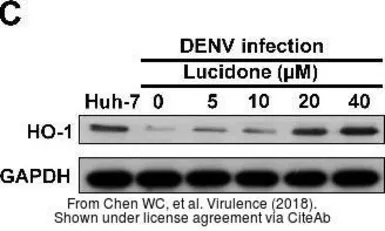

The data was published in the journal Virulence in 2018. PMID: 29338543

The data was published in the journal Virulence in 2018. PMID: 29338543

The data was published in the journal Virulence in 2018. PMID: 29338543

The data was published in the journal Virulence in 2018. PMID: 29338543